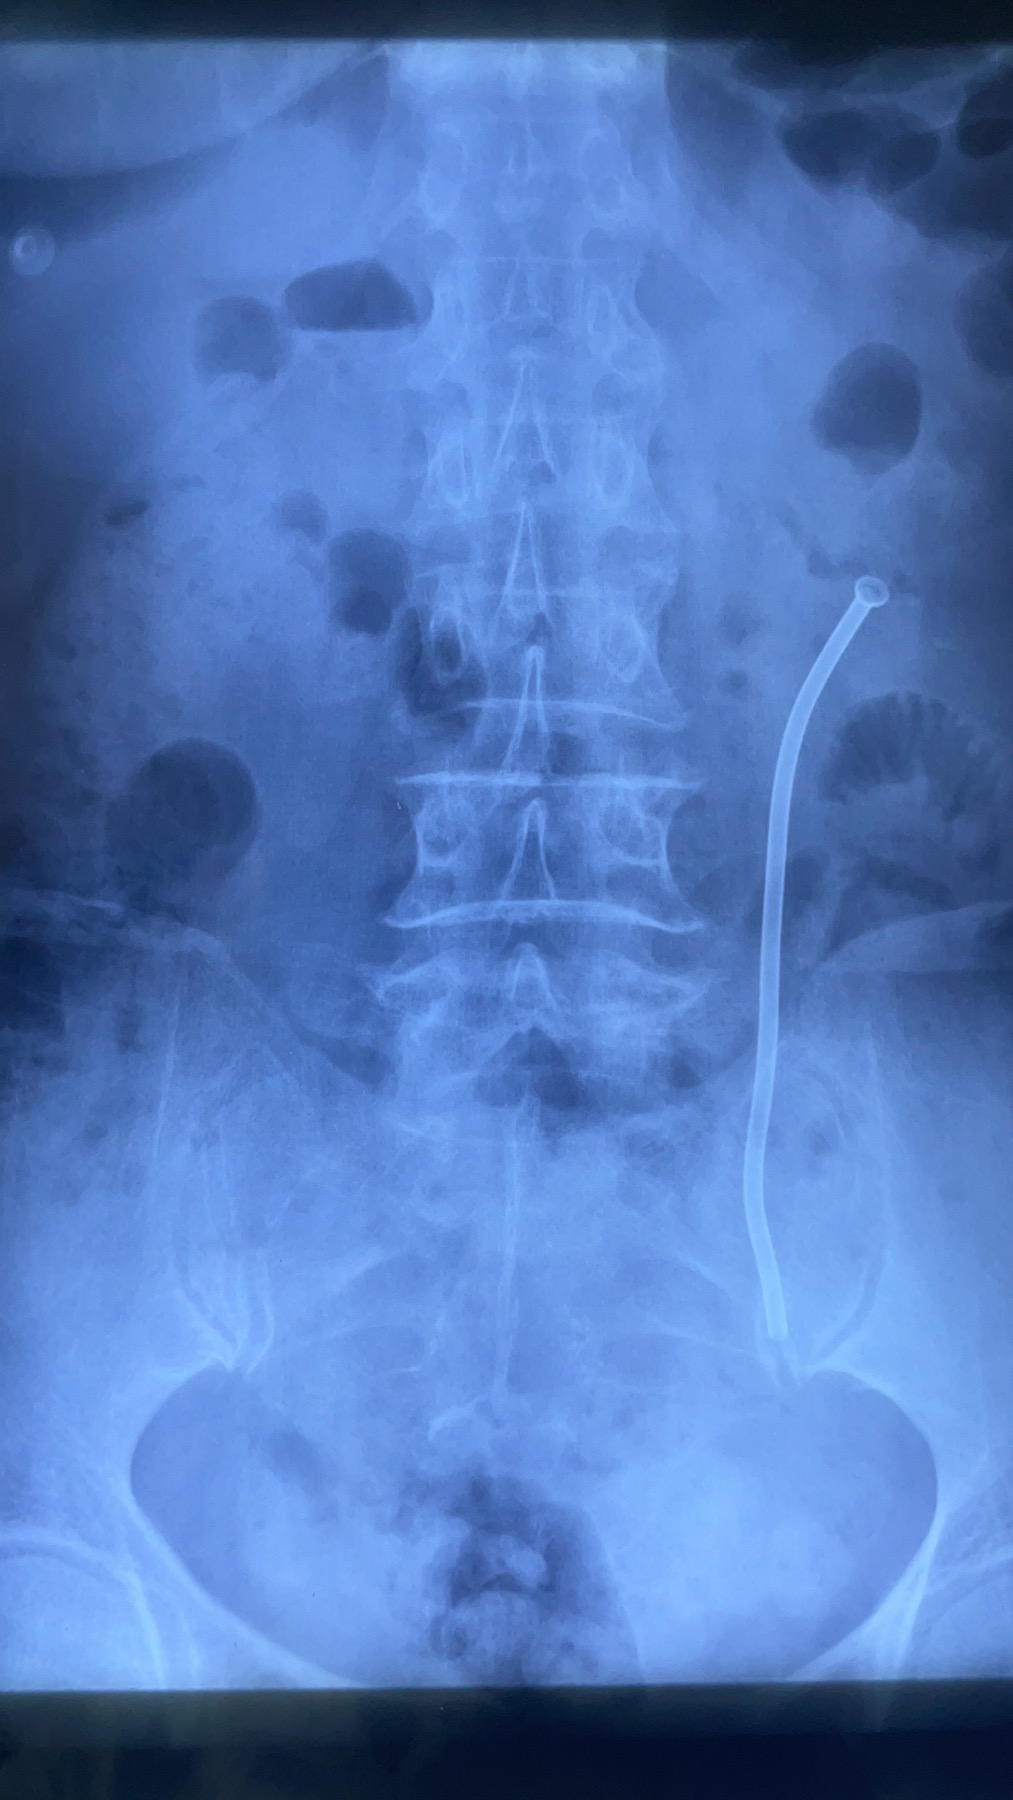

7月11日,我院泌尿外科在北京大学人民医院胡浩教授的指导下,为一名59岁女性输尿管狭窄患者实施了镍钛记忆合金输尿管支架管置入术,本例手术为西北首例。

6年前,陈女士因先天性肾盂输尿管连接处狭窄辗转多家医院,曾经历肾盂成形手术及多次输尿管支架更换术,但输尿管狭窄和反复肾积水导致的病痛始终困扰着她,定期更换输尿管支架管为这个家庭带来了严重负担,通过术中X线定位,精准测量输尿管狭窄段的长度,为陈女士选择适合长度的镍钛记忆合金输尿管支架管(15cm),并准确的放置于肾盂输尿管连接处。在注入65℃热水后,镍钛记忆合金支架成功膨胀,锚定于狭窄处,输尿管再度恢复通畅,手术获得成功。本例手术的成功为陈女士解决了困扰许久的难题。

输尿管狭窄属泌尿外科常见病,原因复杂多样,例如先天发育、肿瘤压迫、子宫内膜异位、自身免疫性疾病、外伤、感染、放疗、医源性损伤等,长期肾积水必然导致肾功能的损害甚至丢失。新型镍钛记忆合金输尿管支架管,是一种螺旋形支架,具有遇热膨胀、遇冷变软的物理特性,其置入操作比较简单、取出容易;同时支架表面覆有特殊涂层,可以减少输尿管上皮细胞生长和结石的形成,可以做到永久性放置。同普通全程输尿管支架相比,镍钛记忆合金输尿管支架是一种局段性支架,不适反应更小,需要更换的次数也更少,同时不会引起返流、膀胱刺激和腰痛等症状。